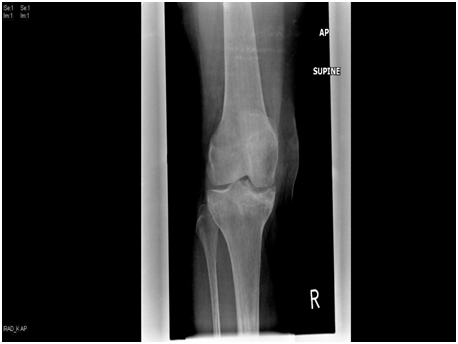

We present a 77 years old Caucasian female with spontaneous onset of pain in both knees for several weeks before presenting to the casualty then to our fracture clinic. There was no history of trauma. The patient is known to have Rheumatoid arthritis (RA) for over 30 years and has been on Bisphosphonate treatment (Alendronate) for over 24 months following the diagnosis of osteoporosis by DEXA scan. Plain radiographs showed subtle linear areas of sclerosis bilaterally in her proximal tibiae (Figure 1 & 2). Magnetic resonance imaging confirmed the presence of extra-articular linear high signal intensity change on T1, T2 with surrounding marrow edema consistent with insufficiency fractures in these areas as well as her right distal femur (Figure 3). These fractures were treated successfully with activity modification and weight bearing in a hinge knee brace as symptoms allows for six weeks along with physiotherapy input. Alendronate was stopped and Teriparatide (Recombinant PTH) was started.

Figure 2 AP & lateral radiograph of the right tibia and distal femur showing an insufficiency fracture with osteosclerotic changes at the medial proximal tibia and distal femur.